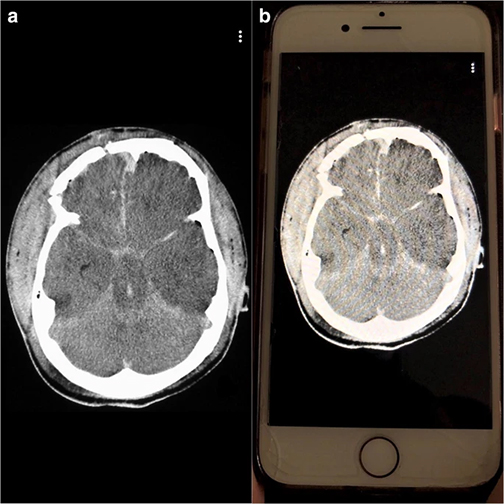

The team compared image analysis and interpretation by radiology residents using Snapchat on smartphones with conventional analysis on a single screen in the resident conference room.

“All cases used were diagnoses considered to require emergent, non-routine communication on the order of minutes to the ordering health care provider,” notes Bradley Spieler, MD, Vice Chairman of Research in the Department of Radiology at LSU Health New Orleans School of Medicine. “As such, these types of diagnoses demand prompt imaging recognition as they are considered critical findings which could result in death or significant illness if not acted upon expeditiously.”The team chose Snapchat, a social media app allowing communication via video and digital images with text messaging functionality, not only because of its popularity with young adults, but most importantly because unlike other image based social media platforms, Snapchat allows for the timing of image visibility by users. The ability to specify the length of time an image is visible to a user (or trainee in this scenario) in rendering an image-based diagnosis creates an intriguing potential for innovation in radiologic curricula, particularly as it relates to assigning a metric to diagnostic performance.

“All residents performed better on Snapchat each week,” says Dr. Spieler, who is also an Associate Professor of Radiology, Internal Medicine, Urology, & Cell Biology and Anatomy at LSU Health New Orleans. “Their accuracy rate was higher using Snapchat than a traditional classroom screen.”